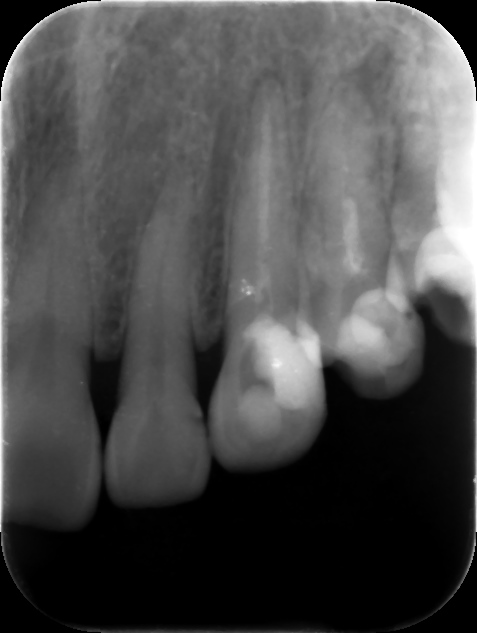

初診時レントゲン。他院で1年以上かけて根管治療を行っているが痛みや歯茎の腫れが引かずに来院。元々は歯髄が生きていた生活歯の抜髄を行ったケース(イニシャルトリート)。同時に3本もの歯を抜髄して長期に根管治療を行う診断に問題があると言わざるを得ない。患者さんは心身ともに疲弊し、歯科治療への不信が高まってしまうのも無理はない。まずは、現状の説明と解決策を提示し、歯科治療への不安を取り除くところから治療が始める。